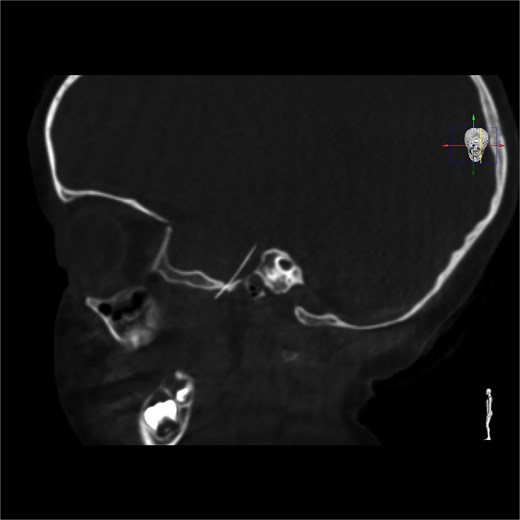

A 4-year-old girl underwent a dental filling procedure to treat a cavity in her right maxillary molar. While blocking the posterior superior alveolar nerve, the distal end of a 31-gauge injection needle broke into her pterygoid musculature. The tip of the needle was not visible, and the dentist could not retrieve it. The patient was immediately brought to the emergency department of our centre, a tertiary referral paediatric hospital. Since the nerve block was effective, the child did not experience any pain. A diagnostic CT scan revealed the needle deep in the pterygomandibular space (Fig. 1), so surgical intervention was scheduled under general anaesthesia in an operating theatre equipped with a low-radiation C-arm cone beam computed tomography (CBCT).

Diagnostic 3D CT showing the needle in the right pterygomandibular space.